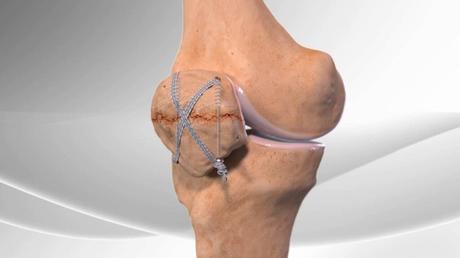

The surgical treatment involves realigning and fixing the bone fragments with wires, screws, or plates.

The surgery may also involve repairing the soft tissues around the patella, such as the tendons and ligaments, that may be damaged or torn by the fracture.

The surgery may be done as an open procedure, where the surgeon makes a large incision over the knee, or as a minimally invasive procedure, where the surgeon makes small incisions and uses special instruments and a camera.

The surgical treatment may also involve removing some of the bone pieces and reconstructing the patella with a graft or a prosthesis, especially for comminuted fractures.